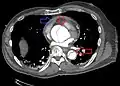

![]() |

| الأشعة المقطعية بالكمبيوتر (CT) | الصورة الرمزية |

| تسلخ الأبهر لحالة تنتمي للمجموعة A في تصنيف Stanford 1 الأبهر الصاعد، التجويف الشرياني الأصلي - 2 التجويف الشرياني الكاذب - 3 الشريان الرئوي 4 الأبهر الهابط - 5 فقرة صدرية | |

يعد تصوير الأوعية الدموية بالأشعة المقطعية بالكمبيوتر من الاختبارات السريعة غير الجراحية التي من شأنها توفير صورة دقيقة ثلاثية الأبعاد للأبهر. يتم التقاط هذه الصور عن طريق أخذ صور مجزأة رقيقة وسريعة للصدر والبطن، والجمع بينها باستخدام الكمبيوتر لتكوين شرائح مستعرضة. لتصوير الأبهر بالدقة اللازمة للوصول إلى التشخيص السليم، يتم حقن مادة تباين معالجة باليود في أحد الأوردة المحيطية (الطرفية). تُحقن مادة التباين وتُجرى الأشعة باستخدام تقنية تتبع الدفقة (Bolus Tracking method). يعد هذا نوعًا من الأشعة المتزامنة مع الحقن بهدف التقاط صورة مادة التباين حال دخولها إلى الشريان الأبهر. ستقوم الأشعة بعدئذ بتتبع مادة التباين أثناء تدفقها عبر الوعاء الدموي.

تتراوح نسبة خاصية الحساسية لهذه الأشعة ما بين %96 و%100، وتتراوح نسبة خاصية النوعية ما بين %96 و%100. من ضمن عيوب هذه الأشعة ضرورة توفر مادة تباين معالجة باليود إضافةً إلى عدم القدرة على تحديد موقع الجزء المتمزق من البطانة الداخلية للشريان.